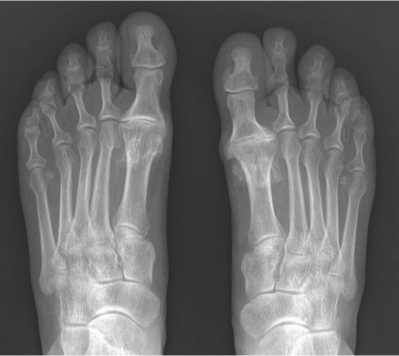

Диагноз «остеоартрит первого плюснефалангового сустава 3–4 ст.» выставлен консультирующим врачом на основании сбора анамнеза, клинического осмотра, результатов рентгенологических исследований (рис. 1).

Рис. 1. Рентгенография дорсально-плантарной проекции одного из пациентов, включенных в исследование: рентгенологические признаки ОА 1 ПФС обеих стоп